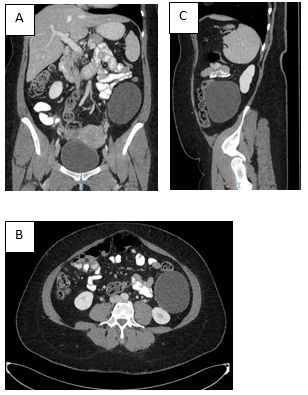

A 43-year-old Caucasian female with past medical history of Diabetes treated with oral medication. Gynecologic history of 5 deliveries with no complications, last one 6 months prior to the consultation. She presented to our clinic with a chief complain of left upper abdominal quadrant pain, moderate and intermittent that started around 2 years and worsened during her last pregnancy. Initial examination revealed mild tenderness at the left upper quadrant and flank, palpable mass that was round with smooth surface, slightly compressible, fixed after deep inspiration and expiration without following respiratory movements (Minkowsky sign: negative). An abdominal contrast-enhanced computed tomography scan showed at the left flank a large retroperitoneal rounded unilocular cystic lesion with thin enhancing walls, measuring 8.5 x 7.4 x 10.2 cm, abutting and displacing the descending colon anteriorly and displacing medially the left kidney, no internal septations, calcification or fat-soft tissue on its interior (Figure 1).

Figure 1 A) Contrast-enhanced computed tomography scan of the abdomen in the coronal plane shows a left retroperitoneal cystic lesion.

B) Contrast-enhanced computed tomography scan of the abdomen in the sagittal plane showing the cystic lesion with no communication to the kidney.

C) Contrast-enhanced computed tomography scan of the abdomen in the axial plane showing the cystic lesion displacing the colon.a .